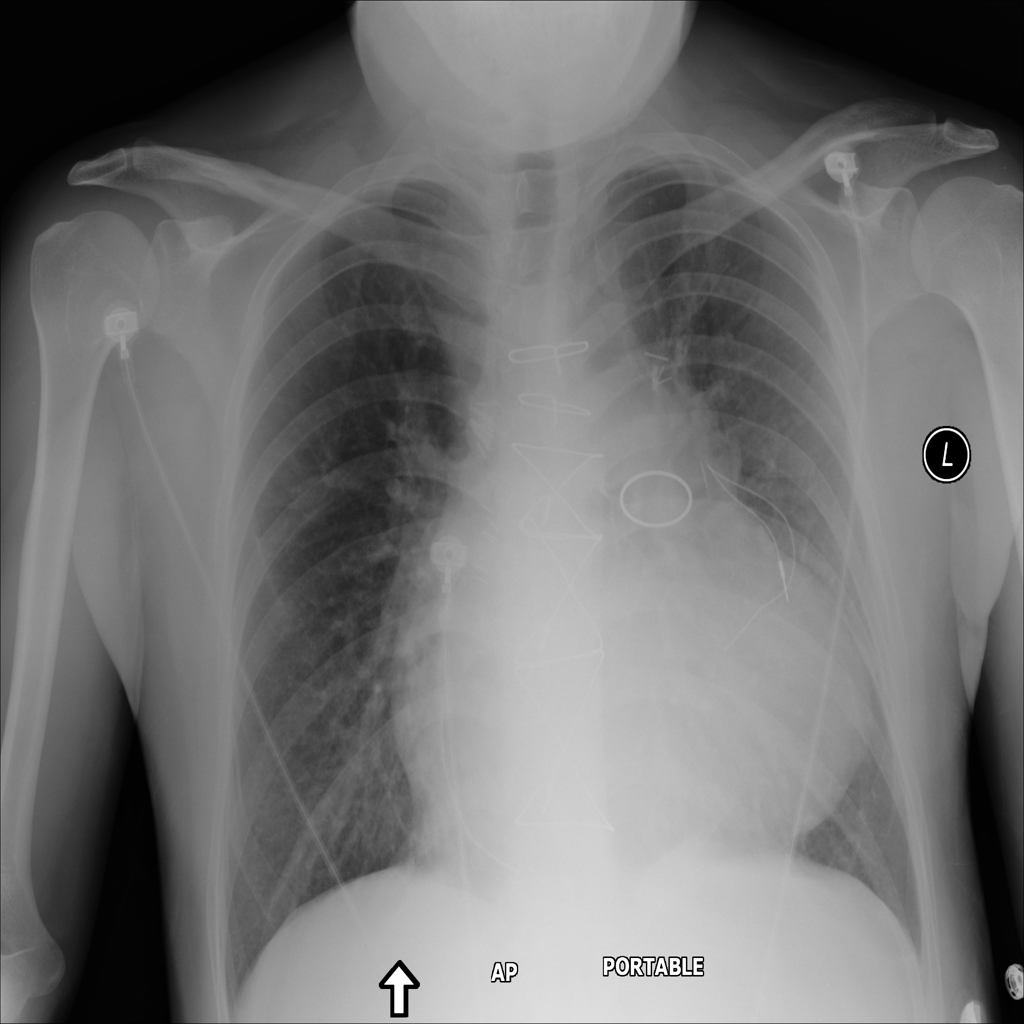

PAT-5092 · IMG-004Cardiomegaly

PAT-5092 · IMG-004

AP